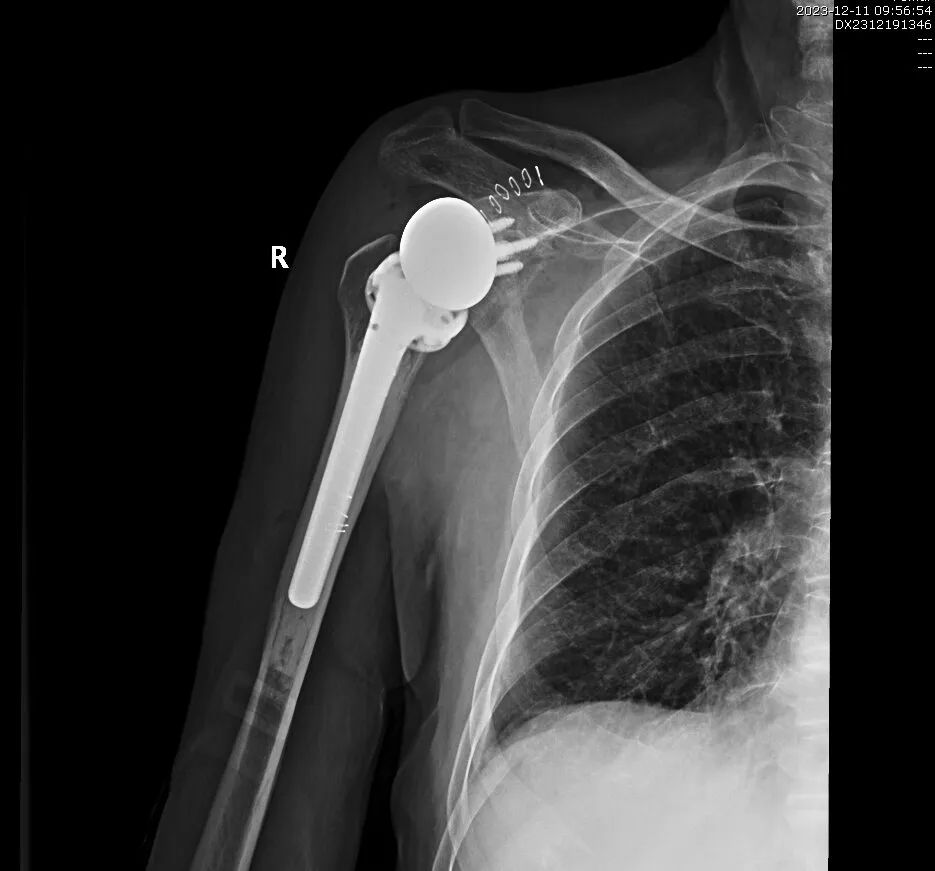

近日,我院关节运动一病区成功完成反式人工全肩关节置换术(reverse total shoulder arthroplasty, RTSA),帮助肩痛患者重获肩关节功能。